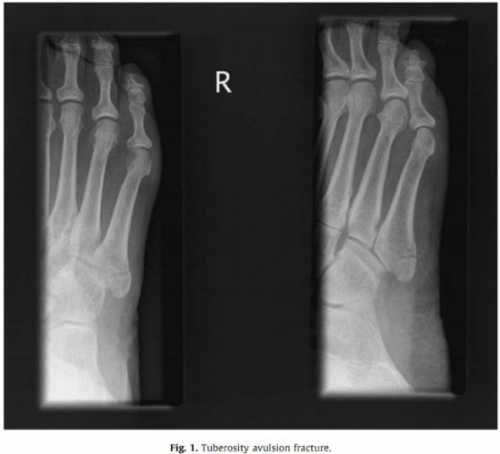

Имеются у пациента хронические заболевания опорно двигательного аппарата. Особенности профессиональной деятельности. Какие меры принимались для снятия болевых симптомов. Перелом пятой плюсневой кости, как и другие деформации стопы, требует обязательного проведения рентгено графического исследования. При необходимости вместо него используется компьютерная томография, показывающая не только деформацию костей, но и состояние мягких тканей и кровеносных сосудов. Врач всегда учитывает, что при стрессовых формах рентген не всегда указывает на патологию, так как она развивается внутри костной ткани, а поверхность остается целой. Терапия заболевания при этой травме может носить как консервативный, так и оперативный характер. Первый используется при закрытых переломах без смещения. При этом применяются мази, гели для снятия отеков, специальная диета и максимальный покой поврежденной конечности.